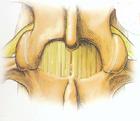

手術徹底切除多可治癒去除局部指甲,甲床淺層即可見。在深層的需切開甲床術中動作要輕柔,以免將包膜弄破不能完整取出。